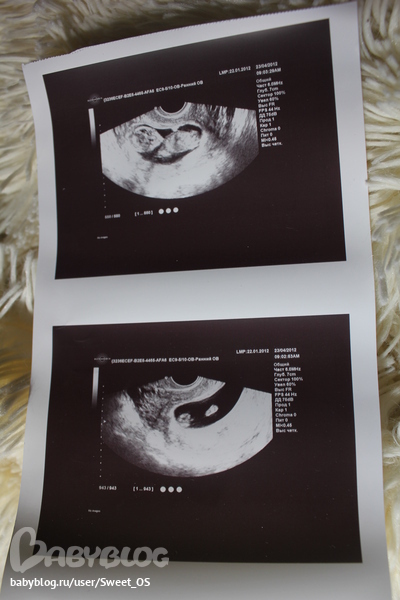

УЗИ в 12 недель

по узи плод на неделю младше акушерского срока... итого вчера было ровно 12 неделек! 52 мм от головы до копчика))))))

но распечатала! вот наша крошка и ее (а может и его) стопа с пальчиками))))

П.с: на втотрой фотке мне померещился мальчик. )

Мне показалось, там слева это попка и что-то маленькое между....у нас просто есть похожая фотка Тимохи. Но может я и ошибаюсь.